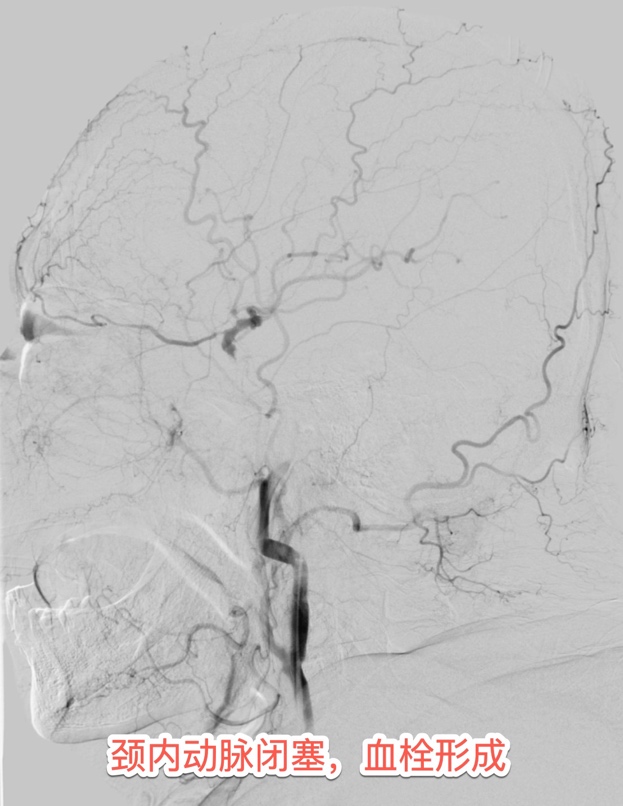

患者住院期间的心电图提示心房颤动病史,发病紧急,没有明显的前驱症状,考虑房颤栓子脱落所致的脑动脉栓塞。介入团队采用最新一代球囊Guilding导管,充盈球囊时可以阻断近段血流,避免血栓逃逸,同时经导管抽吸血栓,可以明显的提高血栓抽吸效率。最终在此先进的医疗技术下精准"抓捕"出大量团块状的暗红色血栓。

在移动监护设备全程护航下,患者被直接推送至CT室。头颈部CTA检查显示左侧颈内动脉完全闭塞——这是给大脑半球供血的核心通道,每延迟1分钟就有190万个神经元死亡。头部CTP提示左侧大脑半球大面积“缺血半暗带”,这部分脑组织是可以被挽救的脑组织,恢复血流可以恢复正常功能的脑组织。情况十分危急,时间就是大脑,越早开通梗死面积越小,预后就越好。